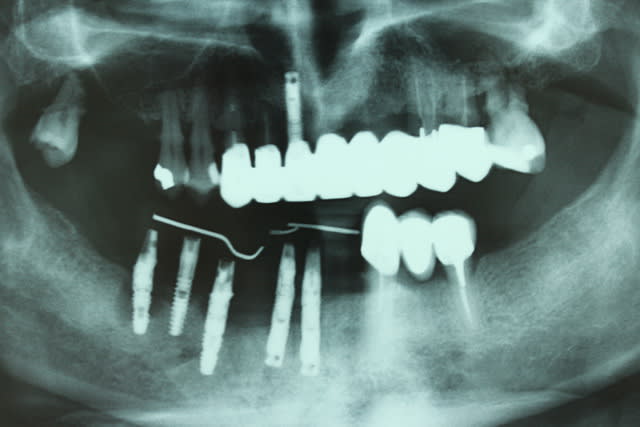

qui peut me dire quel implants on a ici (à par les frialit, facilement identifiés), merci

en haut et devant en bas: nobel mk1

et entre les frialit2 çà doit être un axiom non? (c'est pas très net sur nonol la pano...)

pas facile avec cette radio...

une rétro m'aiderait plus...

c'est pas un ankylos

c'est pas un straumann bone level

les spires qui vont comme çà jusqu'au col m'orientait vers l'axiom...mais si tu dis que c'est pas çà...

un biocom MIS???